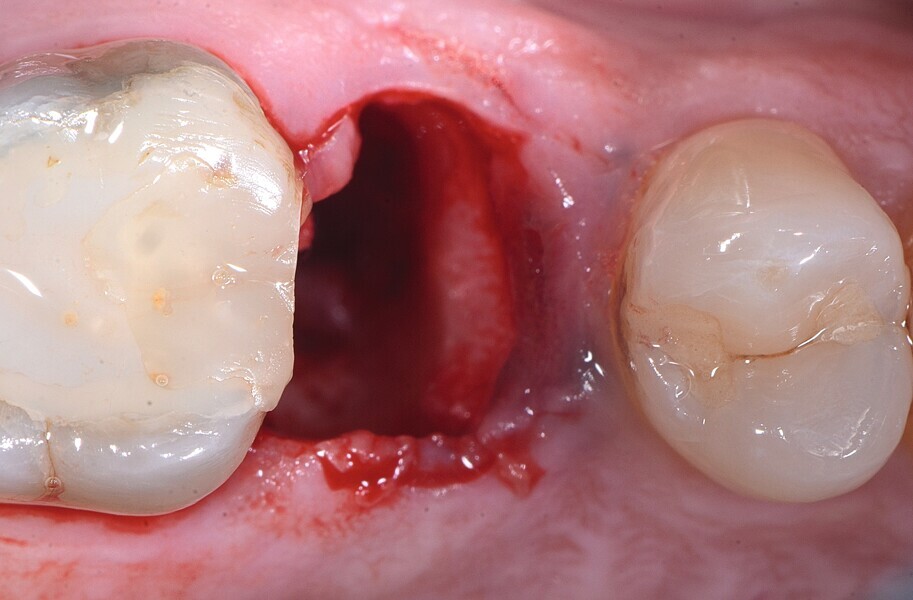

Fig. 12 : Dent irrécupérable.

Fig. 13 : Dent irrécupérable.

Fig. 14 : Dent irrécupérable.

Fig. 15 : Extraction atraumatique.

La pose immédiate d’un implant deux pièces en céramique au niveau tissulaire a été accomplie tout en préservant l’alvéole (allogreffe constituée d’un substitut osseux et protection par une membrane de collagène résorbable). La mise en charge n’a pas été réalisée à ce stade (Figs. 12–24)